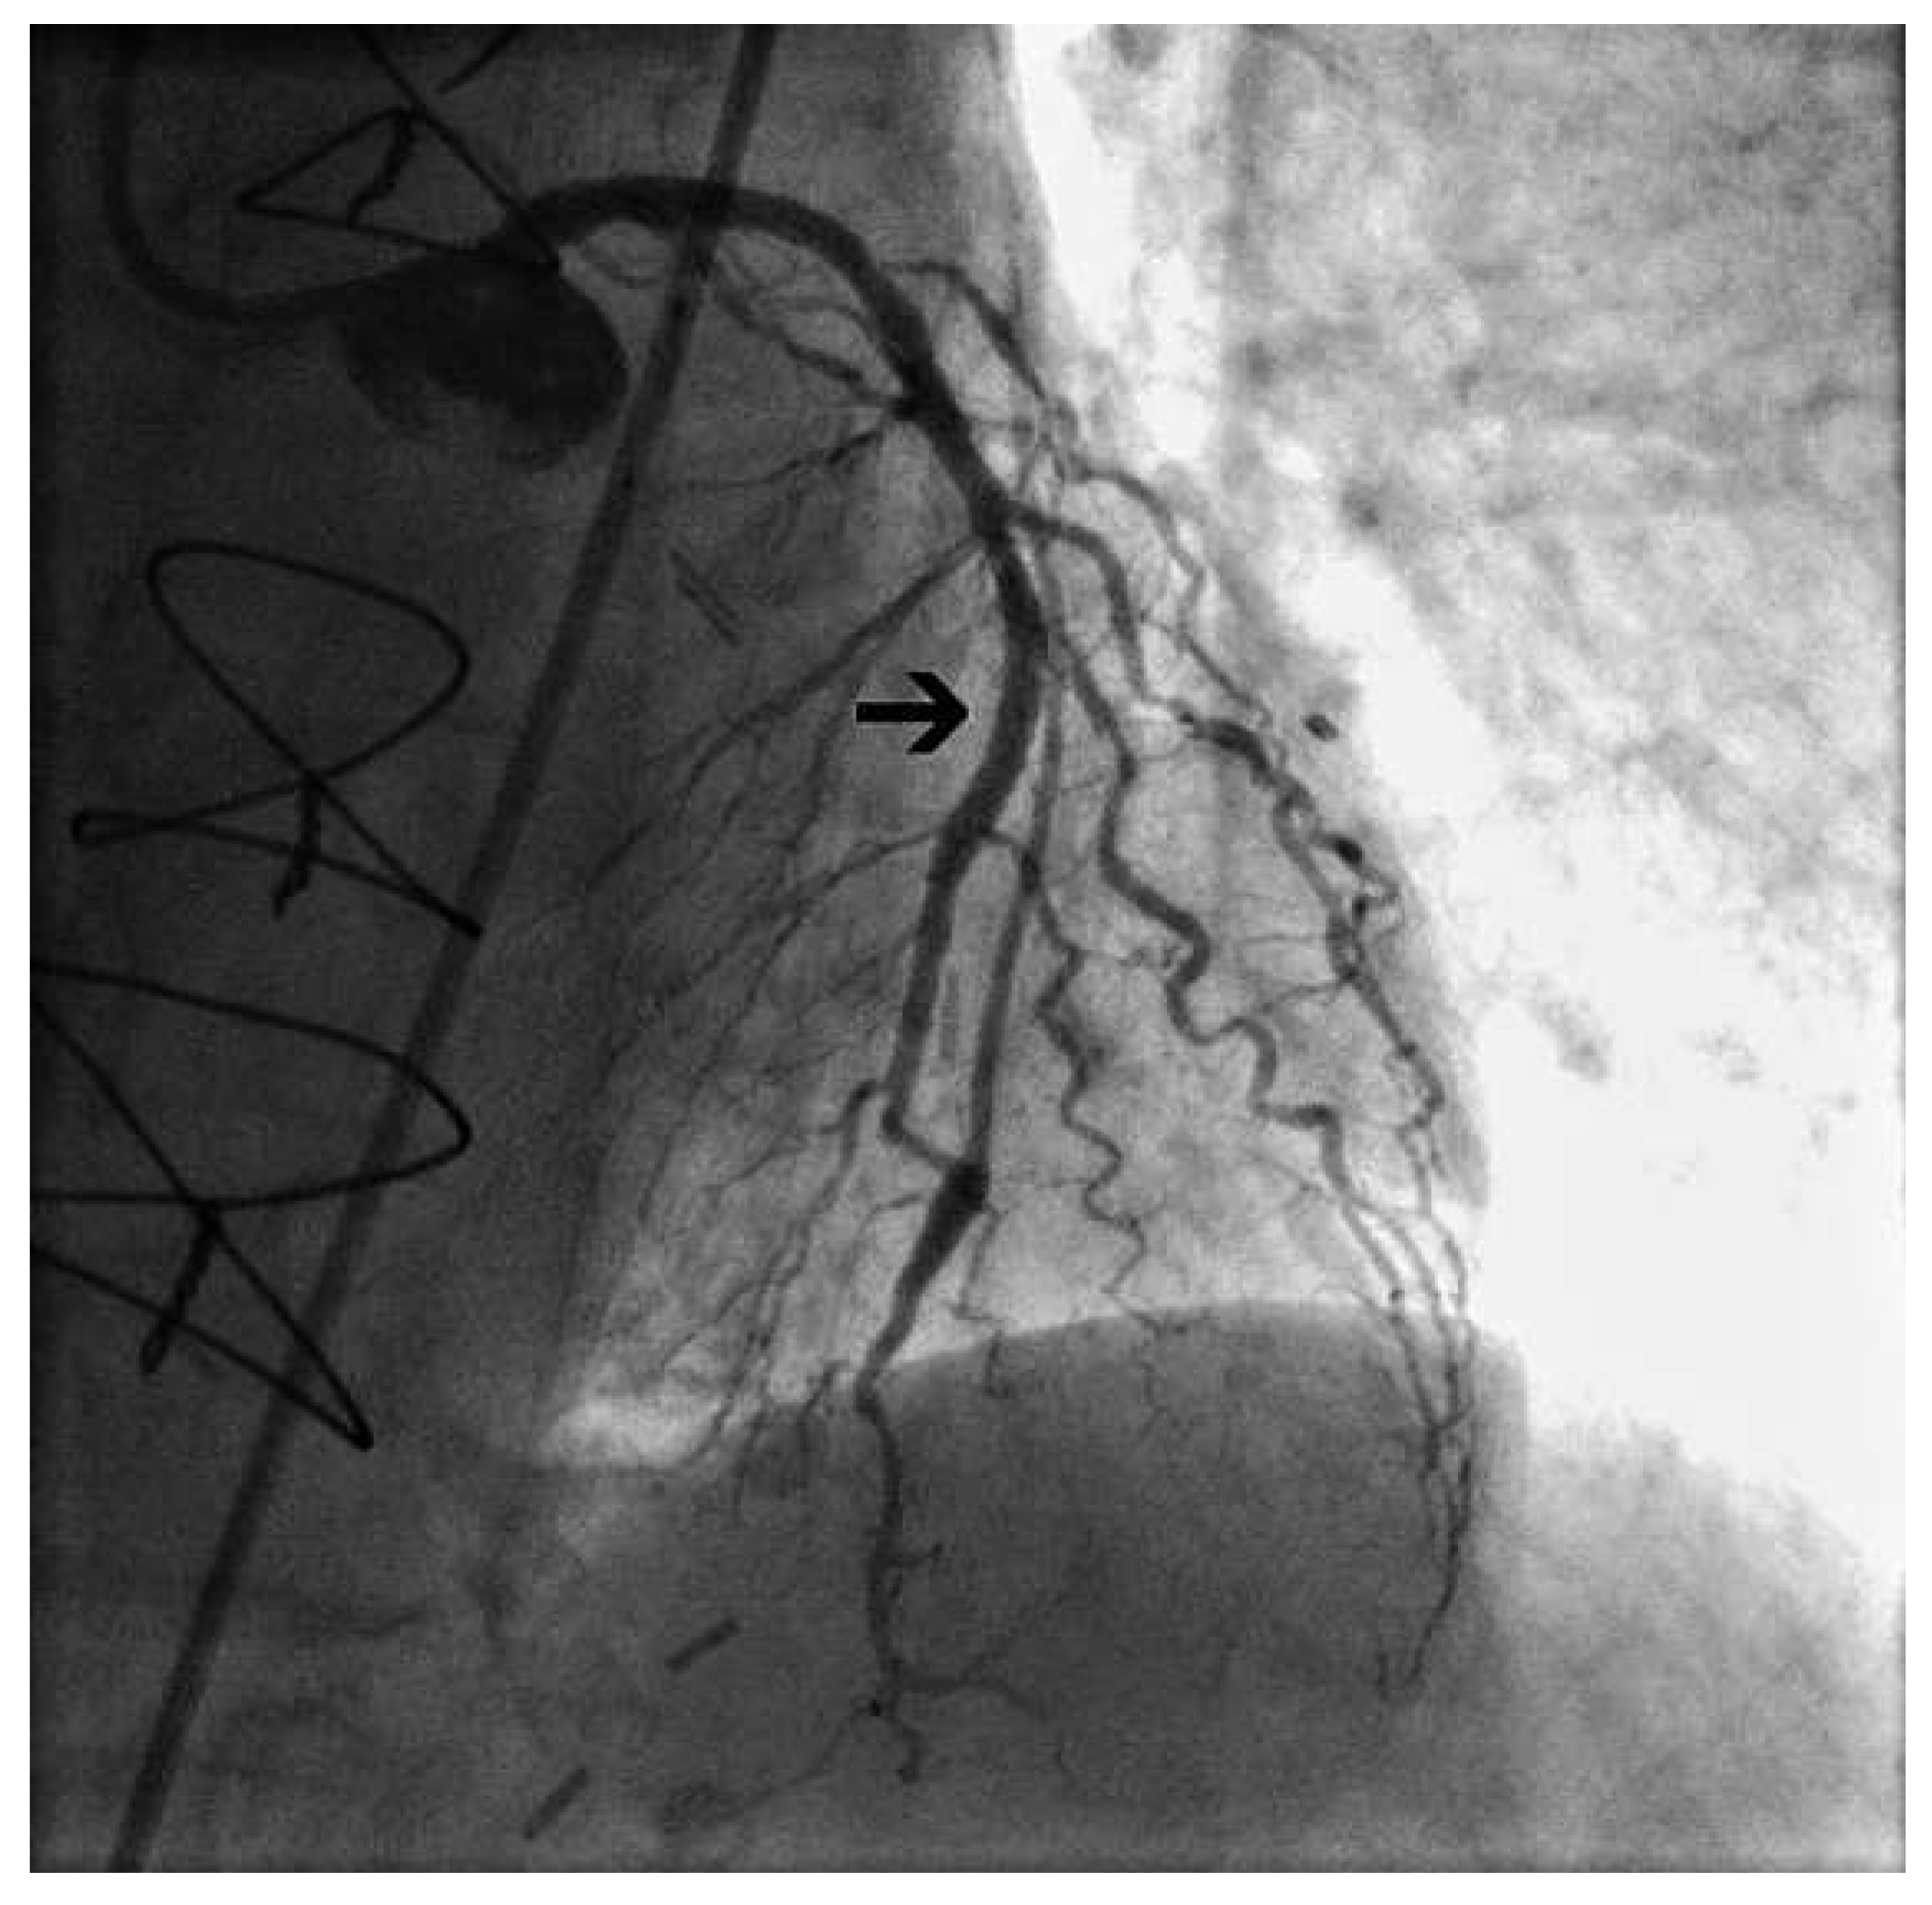

We confirmed the presence of steal due to the ipsilateral AV fistula by occluding the shunt with a pneumatic cuff, which resulted in restoration of antegrade bypass flow during both systole and diastole (Figure 2).

Figure 2. Demonstration of ITA steal due to AV shunt using a pneumatic cuff to occlude the fistula. Deflated cuff: selective injection into the left ITA graft shows an opposition to antegrade flow within the ITA graft (A,B), and a prominent wash-out of contrast medium through the subclavian vein in the late phase (B). Inflated cuff: normal antegrade flow in the ITA graft (C,D), and absence of wash-out of contrast medium through the subclavian vein (D). Black arrows indicate the maximum range of antegrade bypass flow. Black stars indicate the subclavian vein.